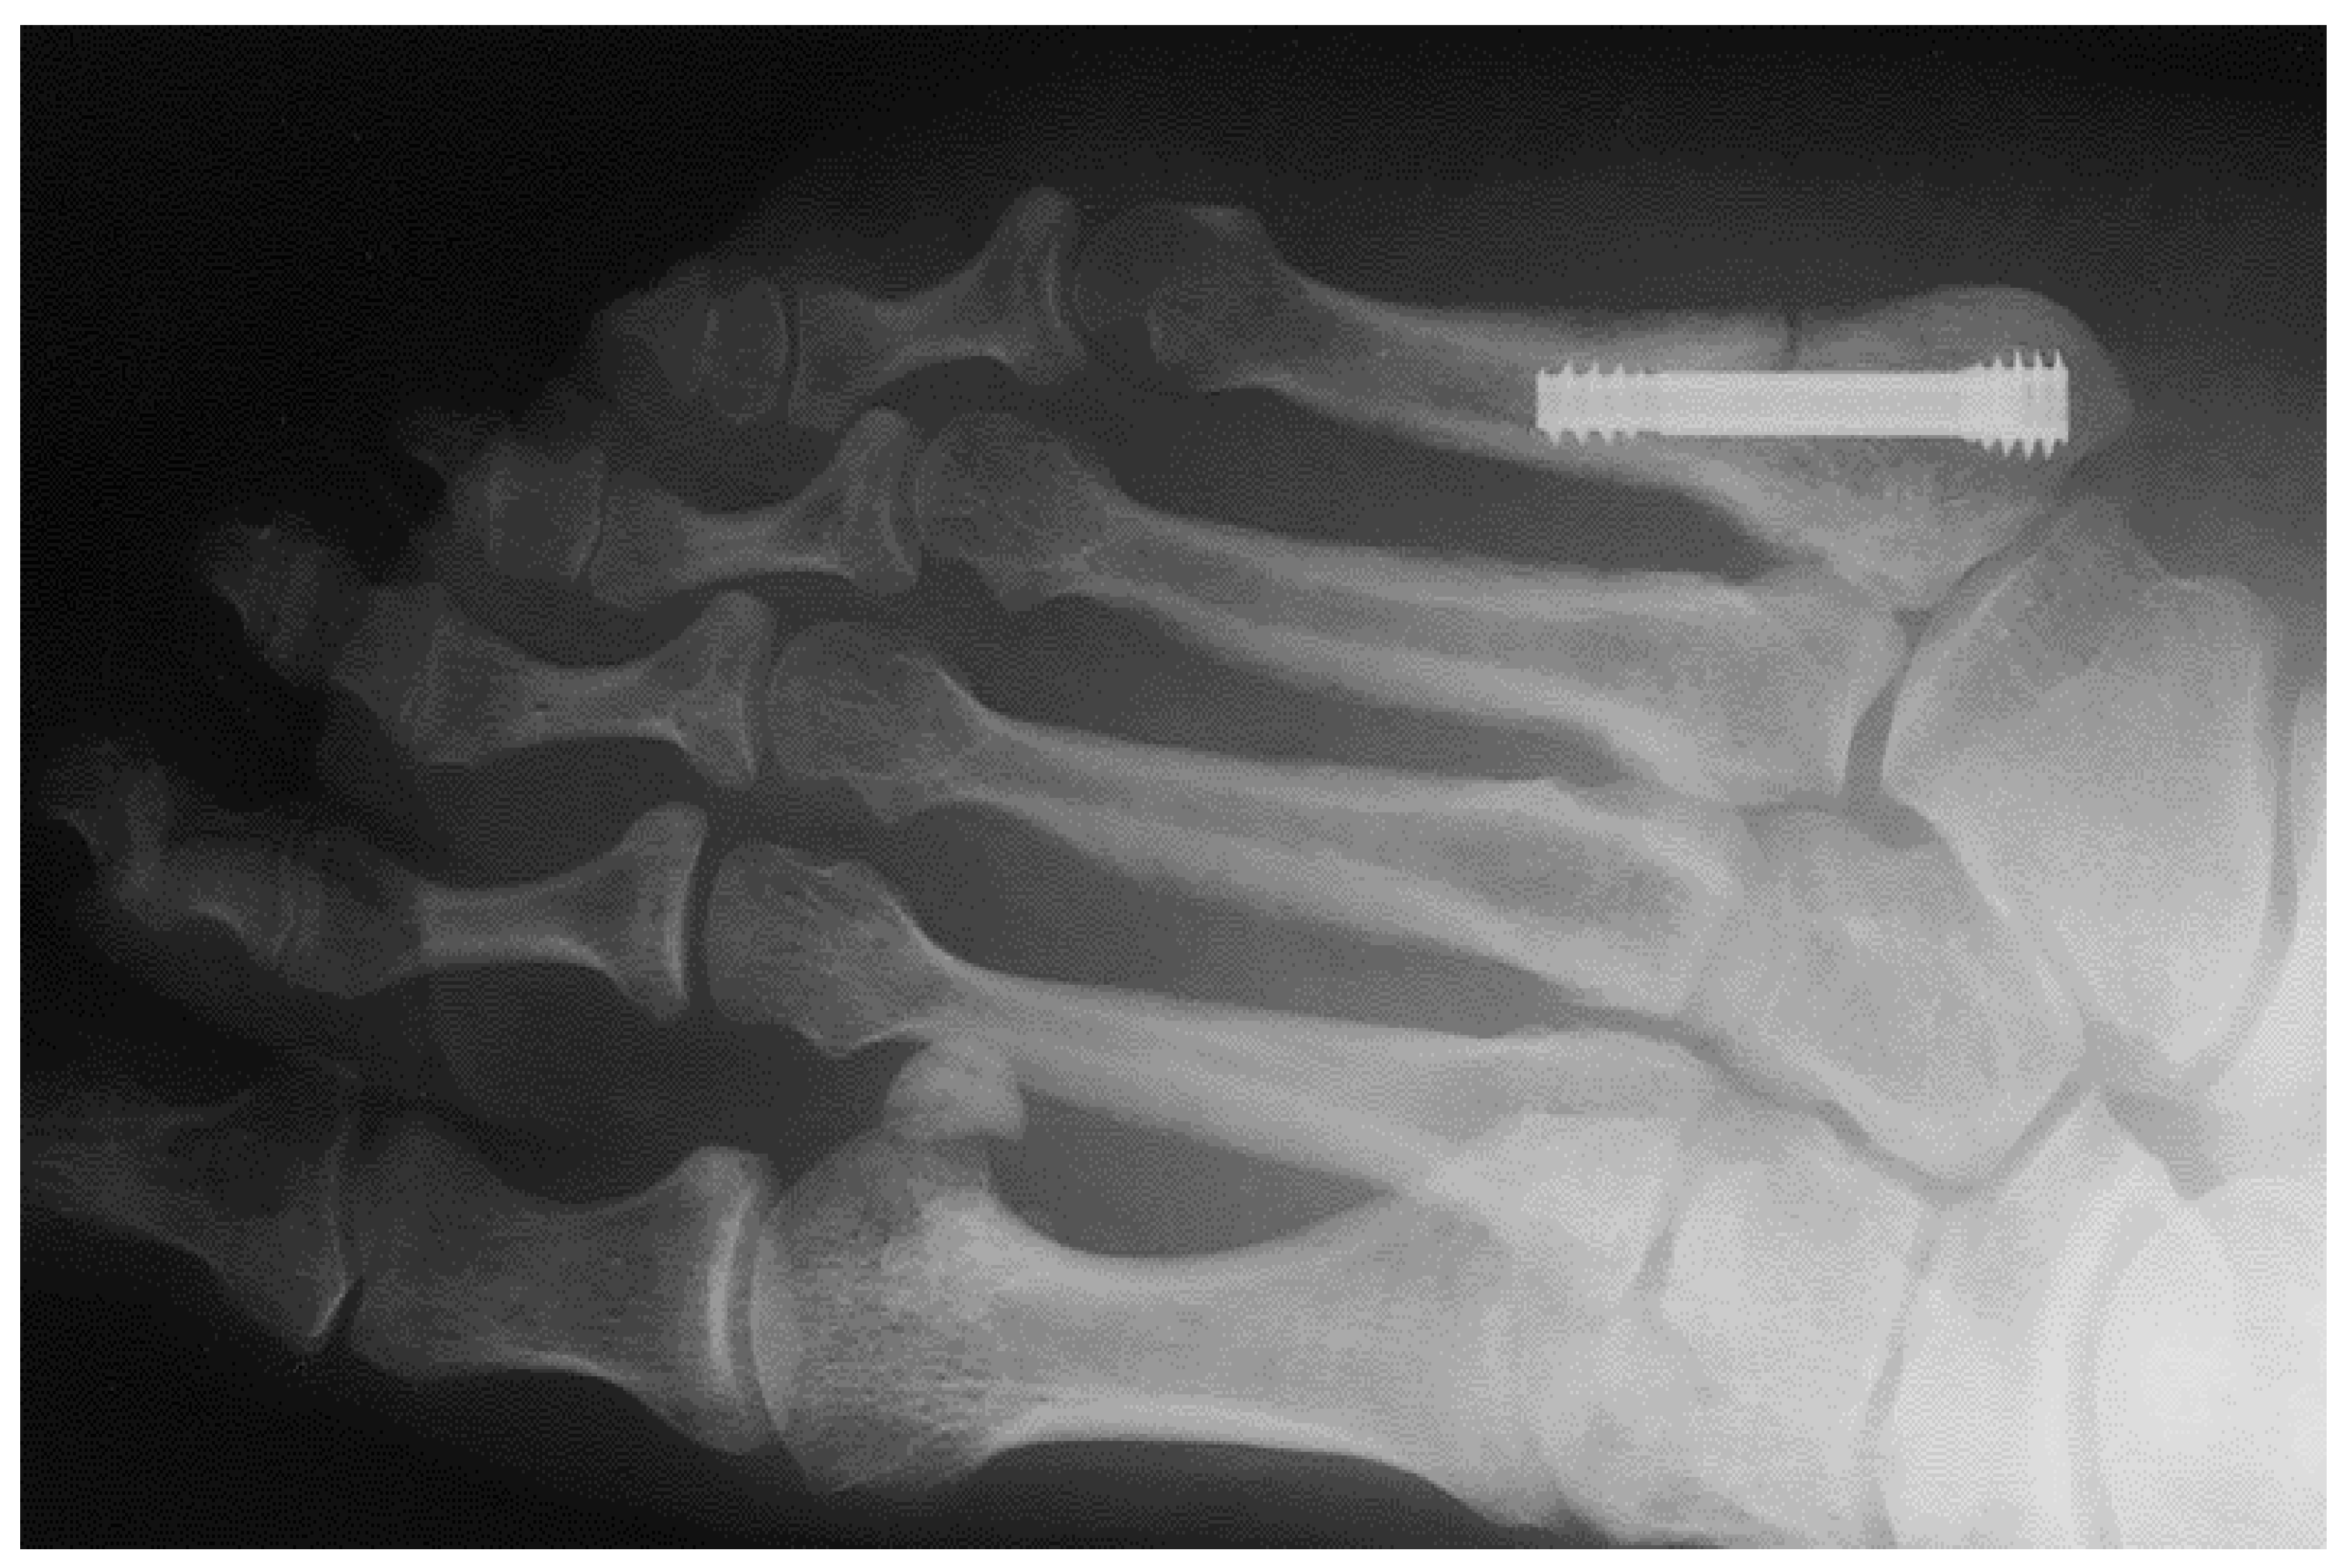

Figure 1 shows an X-ray snapshot of the fixation of a fifth metatarsal fracture with a headless screw. Metatarsal fractures are the most common fractures of the leg, the most common among them being the fifth metatarsal fracture. Metatarsal fractures are mostly caused by direct impact (car accident, fall, etc.) or during sports (typical injuries of football players, etc.). There are multiple types of metatarsal fractures, such as the Jones fractures, proximal diaphyseal, or fatigue fractures. Interested readers may find more information in [5,6].

Figure 1.

Application of a headless screw to the fifth metatarsal bone.